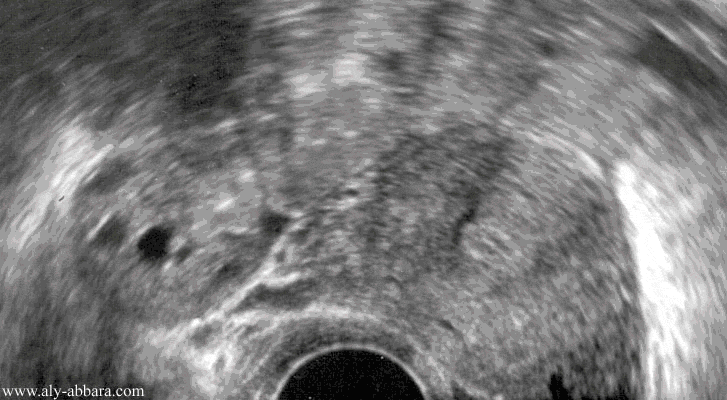

Coupe échographique traversant un ovaire et utérus normaux